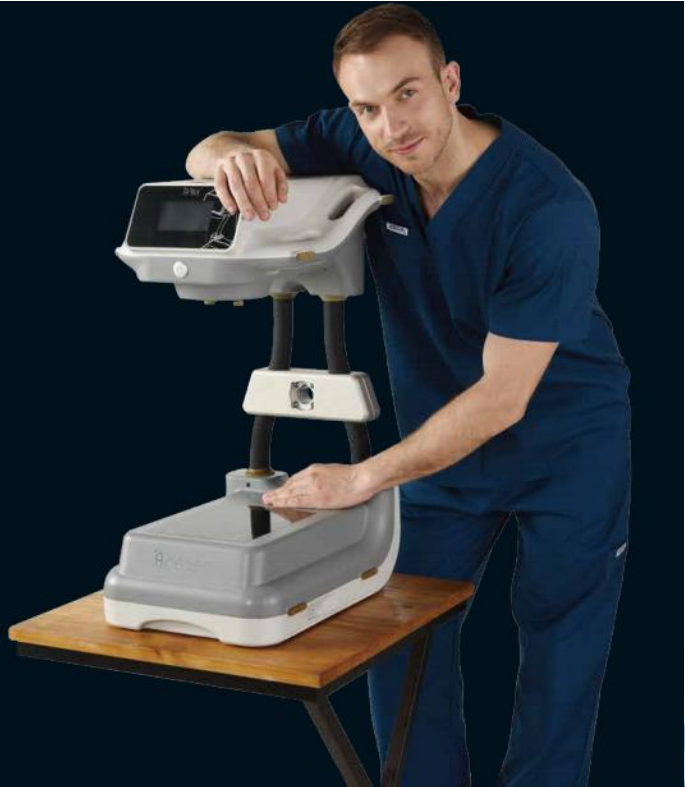

KD-CMN100

移动式数字MINI C形臂

KD-CMN100 是一款灵巧便捷的新型数字 X 射线影像系统,由康达洲际自主研制开发,用于诊断需要的数字化透视和摄影,适用于临床医疗/运动损伤/科研等领域。

紧凑灵活的台式C臂结构设计

便捷、精巧、灵活是 CMN100 带给用户最直观的体验和感受。 从整机的结构设计以及占地和重量考虑,均立足于手足外科的临床应用需要。

紧凑的设计强化设备的流动性、通用性和灵活性

紧凑的 MINI C 臂设计,比普通 C 形臂移动性能更好,方便患者的检查并提高被检对象的流动性;

简易的操作流程和 83KG 的整机重量,普通大夫或护士单人即可驱动操控;

不足 1 平米的空间占地,可以自由穿梭在手术室间甚至病床旁。

更符合手足外科临床开展的 “ 台式 ”C臂结构设计

与常见的“轴式”C 臂结构设计不同的是,CMN100 采用全新的”台式”C 臂结构与”轴式“显示控制相结合的操作控制。

根据手足外科的临床应用特点,医生是通过改变患者的肢体角度来改变投照角度、而无需调整 C 臂角度,

即通常医生将探测器平面作为一个“操作台”,不需要像其它 C 臂那样改变 C 臂角度,显然这样的台式结构更利于手术操作和图像观察,使得设备设计能够充分与手术场景融合。